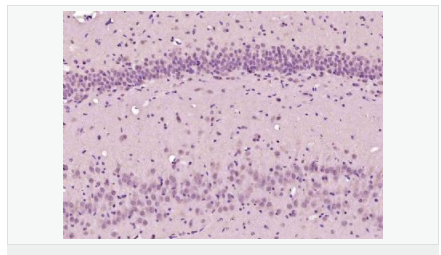

產(chǎn)品介紹Involved in the formation and segmentation of paraxial mesoderm. Has the regulatory capacity to specify ventrolateral (including future paraxial), but not dorsal (future axial), mesoderm phenotypes. Seems to be an upstream regulator of at least some elements of the Notch and Delta signaling pathway.

Involved in specifying the paraxial, but not dorsal, mesoderm. May regulate the expression of T-box transcription factors required for mesoderm formation and differentiation (By similarity).

Subcellular Location:

Nucleus.

Similarity:

Contains 1 basic helix-loop-helix (bHLH) domain.